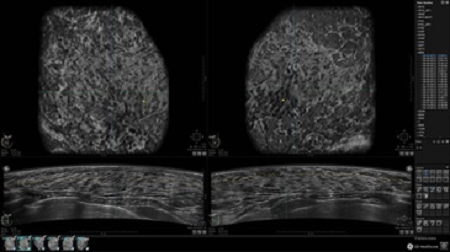

GE INVENIA ABUS – это современный УЗИ аппарат, который создан для точной и эффективной диагностики сканирования с высокой плотностью молочных желез. Выявляемость патологий раковых и предраковых стадий заболевания составляет 55%, что в конечном счете позволяет ставить врачу точные и своевременные диагнозы. Традиционные методы использования маммографии не показывают такой выявляемости, ограничиваясь лишь 3-38%.

УЗИ-аппарат GE INVENIA ABUS позволяет проводить максимально операторонезависимые процедуры, что значительно снижает риск неправильной постановки диагноза и сопутствующие издержки на обработку информации. Система готовит отчет в течение 3-х минут после сканирования, это безусловное преимущество по сравнению с обычным УЗИ сканером.

• датчик с изогнутой апертурой для качественного исследования

• сканирование одной грудной железы в трех проекциях не более 60 сек.;

• обработка результатов за три минуты.

Возможности встроенной УЗ-системы:

• Увеличение или уменьшение степени сжатия грудной железы;

• Функция автоматического сканирования активируется одним нажатием;

• Возможность отмены сканирования;

• Глубина проникновения УЗ-лучей – до 50 мм;

• Одно детализированное изображение можно получить менее чем за 1 минуту

• Многорядная светодиодная подсветка;

• Встроенный сверхширокий вогнутый датчик С15-6ХW.